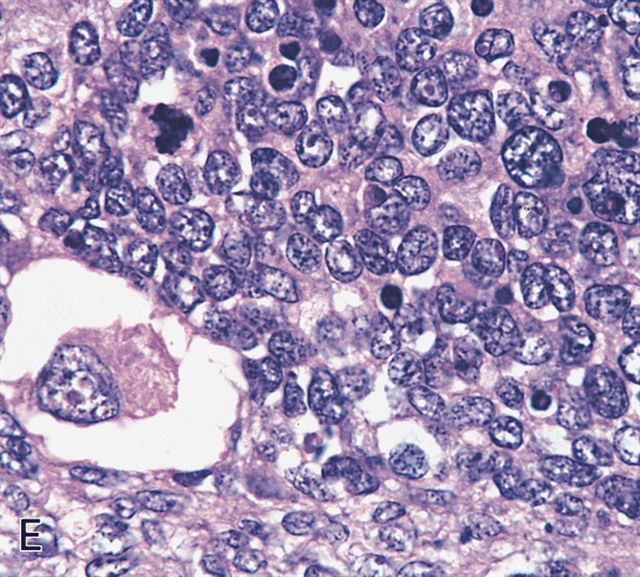

Microscopic (histologic) images

Contributed by Erdener Özer, M.D., Ph.D. and Mark R. Wick, M.D.

Contributed by Carolina Martinez Ciarpaglini, M.D., Ph.D. (Case #276) - tonsillar mass

AFIP images - anaplastic rhabdomyosarcoma